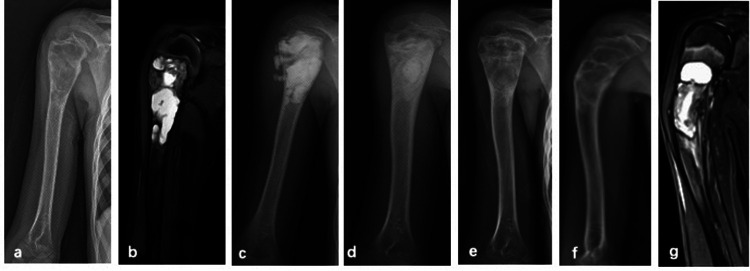

Methods: All patients underwent the PAIB procedure. Postoperative evaluation involved radiographic assessment to monitor recurrence and identify potential complications, with magnetic resonance imaging (MRI) performed when clinically indicated.

Results: In this cohort of 36 patients with SBC treated using the PAIB technique, the mean follow-up duration was 33.5 months (range: 12-66 months). Recurrence occurred in 6 patients (16.6%), including one case complicated by a pathological fracture. Five of the recurrent cases underwent repeat PAIB procedures, resulting in complete resolution in two patients. Postoperative imaging revealed small residual cysts in three cases. Bone healing was successfully achieved in 32 patients. Graft bone exudation, identified as a potential risk factor for recurrence, was observed in seven patients. All patients exhibited satisfactory functional outcomes throughout the follow-up period.

Abstract Image